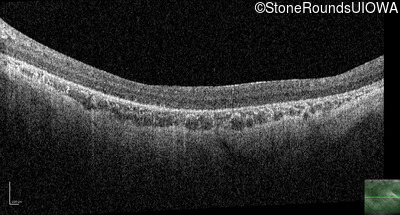

Optical Coherence Tomography - Left - 20/500 sc

Exemplar / OCT Stack